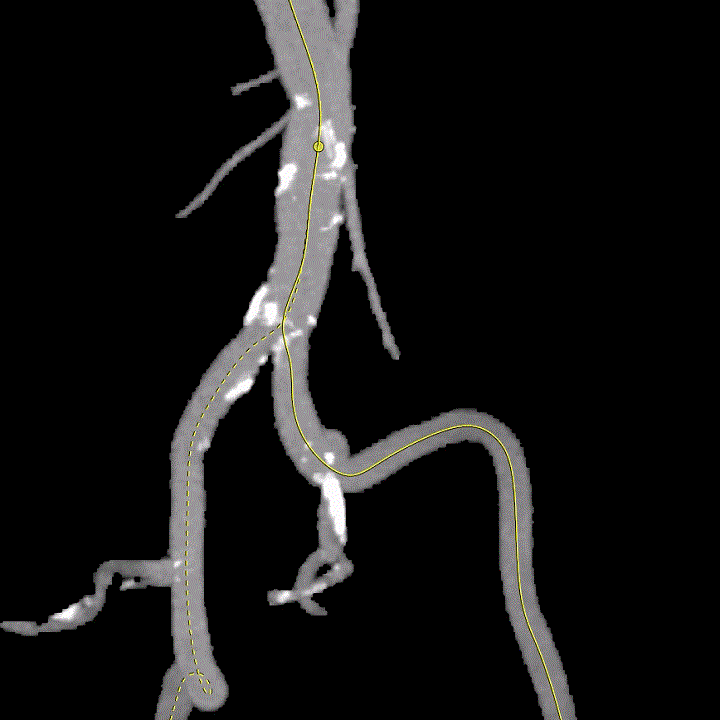

术前经详尽评估患者病情,通过CT重建观察到既往植入的自膨式TAVR瓣膜呈椭圆形,测量瓣环直径,及双侧冠脉开口高度,并评估外周血管入路。由于患者外周血管钙化严重且迂曲,经外周血管途径有较大风险,决定对该病例采用经心尖途径行TAVR瓣膜内 “瓣中瓣”手术。但第二次经心尖途径又将面临心脏、肺、胸壁肌肉组织的粘连,手术难度大。经术前反复讨论和仔细测量毁损TAVR瓣膜的平均内径和冠脉开口高度,决定选用25号 Renato球扩瓣膜。Renato球扩式瓣中瓣可以提供更强的径向支撑力,瓣架高度低,术前模拟植入评估显示冠脉梗阻风险低。手术过程顺利,最终瓣中瓣植入位置理想,功能表现出色,主动脉根部造影及经食道超声观察无瓣中及瓣周反流。